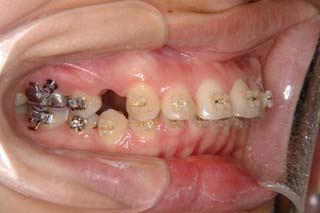

診断名:叢生を伴う上顎前突

使用した主な装置名:TPB、マルチブラケット装置、歯科矯正用アンカースクリュー

抜歯/非抜歯および抜歯部位:抜歯(上顎左右第一小臼歯)

かなり強い上顎前突を示します。その他の問題はなさそうですが、小臼歯抜歯だけでは上顎前突に対応しきれそうにありません。上顎大臼歯に最大限の固定が必要と考えられましたので、上顎左右の臼歯部に計2本の歯科矯正用アンカースクリューの植立を検討してみました。